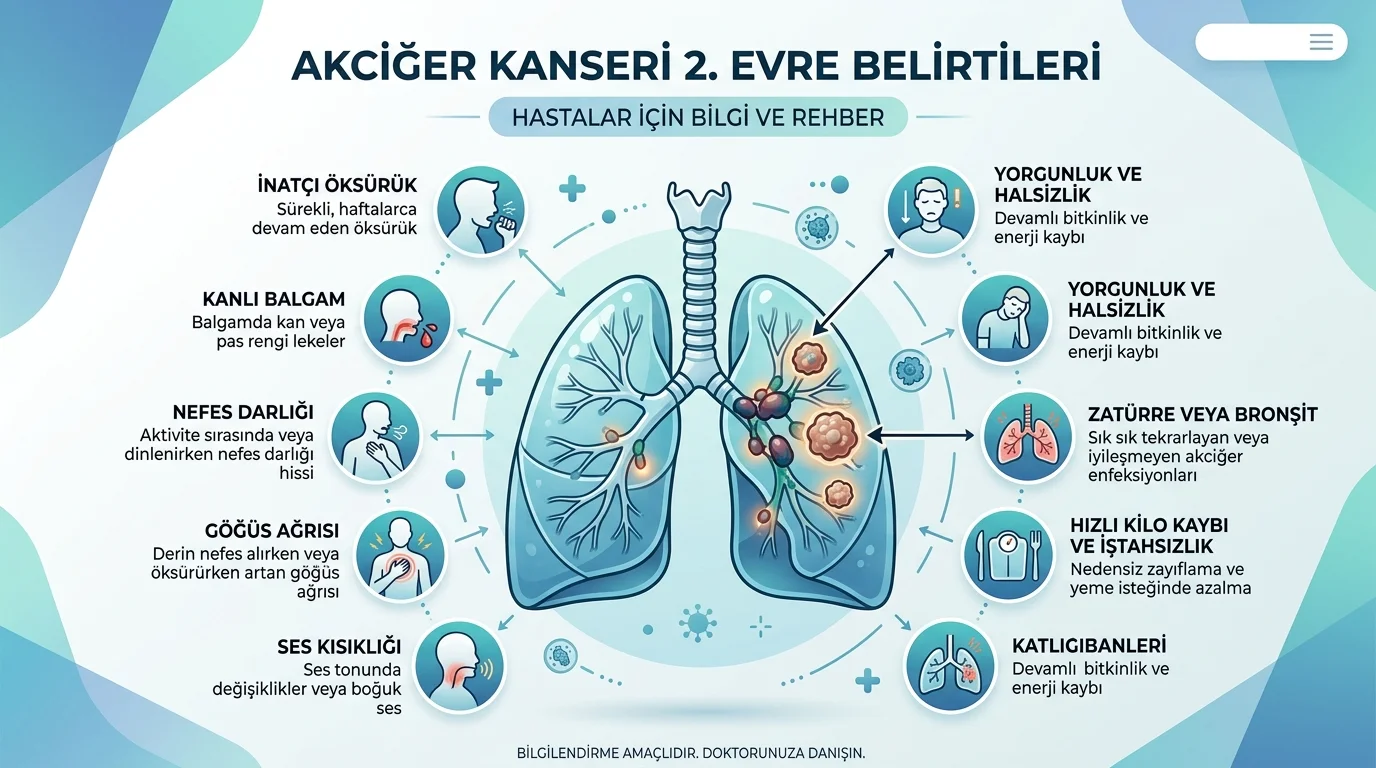

EVRE 2

EVRE 2

Tümör biraz büyümüş veya yakındaki lenf bezlerine yayılmıştır.